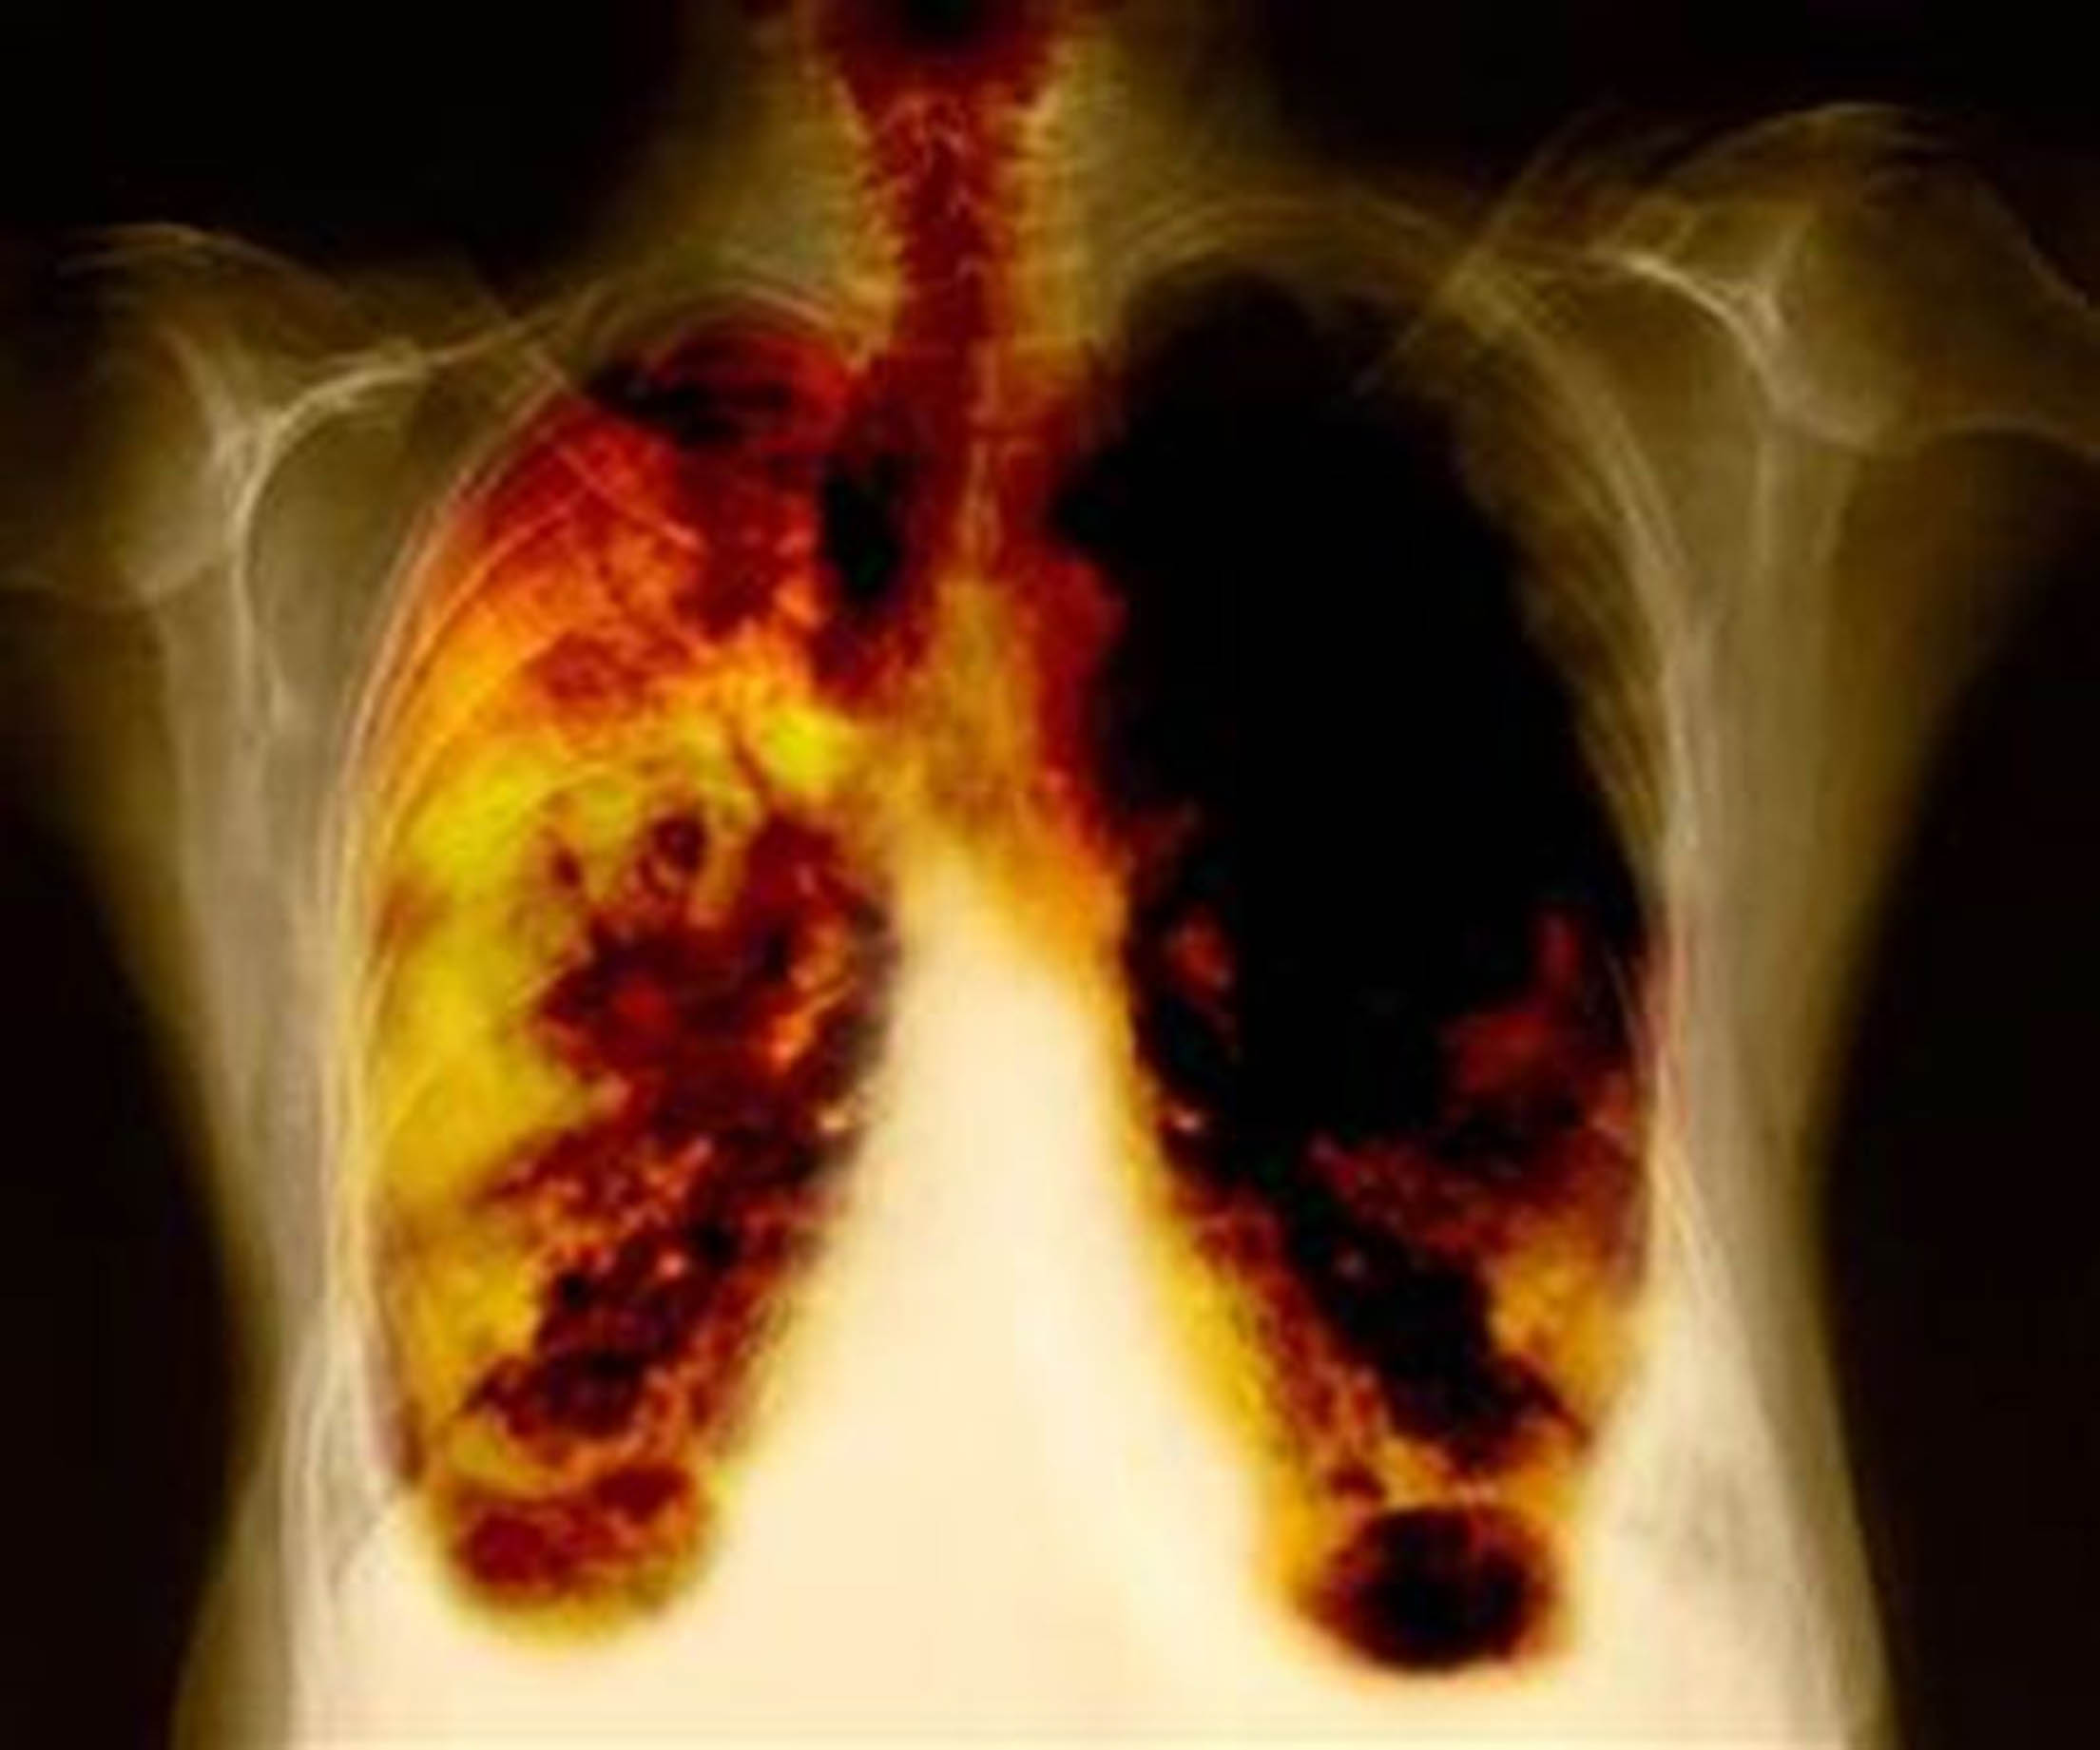

América Latina, octubre de 2020– El cáncer de pulmón es el tumor más letal en América Latina, responsable por 86 mil muertes por año en la región y causante de alrededor de 1,8 millones de víctimas globalmente.

Identificada tardíamente en 85% de los pacientes en América Latina, la enfermedad tiene pocas posibilidades de cura, con una tasa de supervivencia de cinco años en alrededor del 18% de los casos.

El gran desafío es lograr un diagnóstico temprano, se conoce que cuando el tumor es identificado en estadios iniciales, la tasa de supervivencia a cinco años aumenta significativamente, alcanzando hasta el 56%.